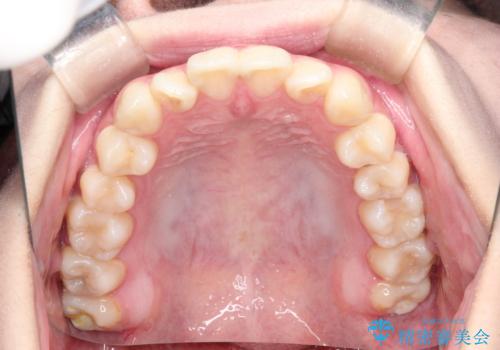

- 上下の前歯に捻れ(捻転)とガタつき(叢生)が見られます。

上の2番目の前歯の捻れに関しては、元々歯の大きさが小さい歯であるため、マウスピースにて力がかかりにくく、捻転の改善が一般的に難しくなりがちです。

マウスピース枚数 初回33枚 +追加22枚 +追加31枚

概ね2年で治療完了しました。

マウスピース矯正の特性として動かすのが難しい歯を含むケースでしたが、当院独自の工夫を随所に盛り込み、狙い通りの治療結果が得られました。